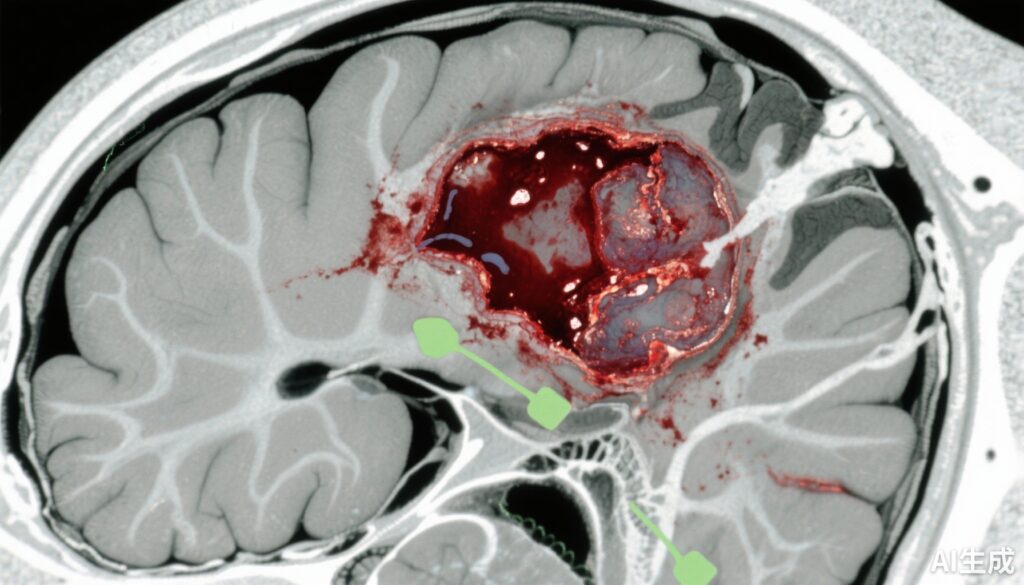

外傷性脳損傷(TBI)は世界中で重要な死因や障害の原因であり、急性硬膜下血腫(ASDH)は最も深刻な頭蓋内病変の1つです。ASDHは、頭部外傷により硬膜と脳表面の間に出血が生じ、頭蓋内圧が上昇し、脳ヘルニアを引き起こすことがあります。従来の管理方法は、マスエフェクトと二次的な脳損傷を軽減するために緊急手術的除去を行うことですが、損傷の重症度や患者要因の多様性により、即時手術が保存療法よりも優れているかどうかは不確定です。この不確定性は、臨床実践における変動を生み出し、ASDHの管理においてリスクと利益をバランスさせる最適な治療戦略を明確にする未充足の医療ニーズを強調しています。